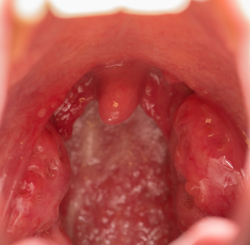

Holes In Tonsils Causes Symptoms And Treatment

Holes In Tonsils Causes Sore Throat And More

Holes In Tonsils What Are They And How To Get Rid Of Them